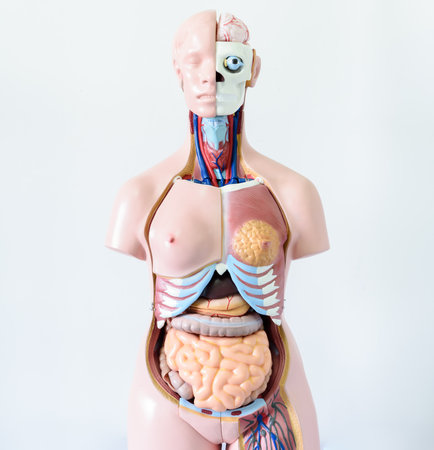

Anatomy human body model in the class room on white background.Part of human body model with organ system.Human muscle model.Medical education concept.

Anatomy human body model in the class room on white background.Part of human body model with organ system.Human muscle model.Medical education concept.

Anatomy human body model in the class room on white background.Part of human body model with organ system.Human muscle model.Medical education concept.